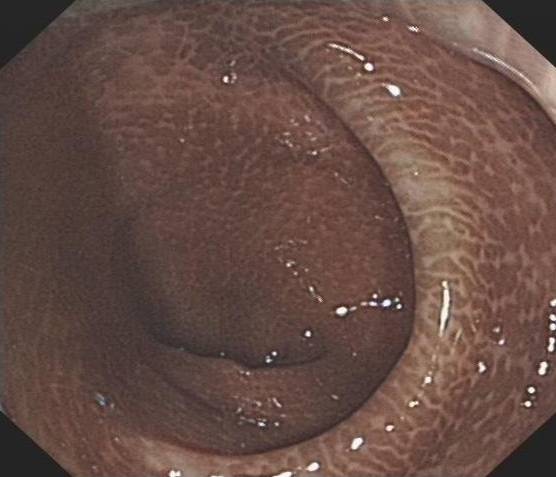

无图无真相,来看着这个图!

正常人的结肠VS 黑变病结肠▲

辣不辣眼睛?但是,结肠黑变病还不是最可怕的,最可怕的是滥用泻剂对于肠功能和肠动力的损害,这些是不可逆的!